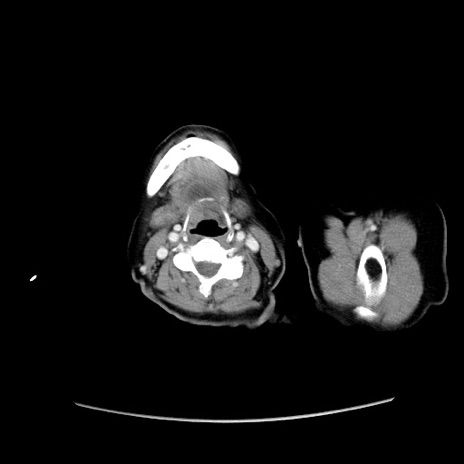

症例19(横断像)

【症例】80歳代女性

【主訴】下腹部痛

【現病歴】約8時間前より下腹部痛の出現あり、救急外来受診。

【既往歴】両側付属器切除

【身体所見】意識清明、下腹部正中に手術痕あり、その部位に一致して圧痛と反跳痛あり。腸蠕動音は亢進。

【データ】WBC 9300、CRP 0.15